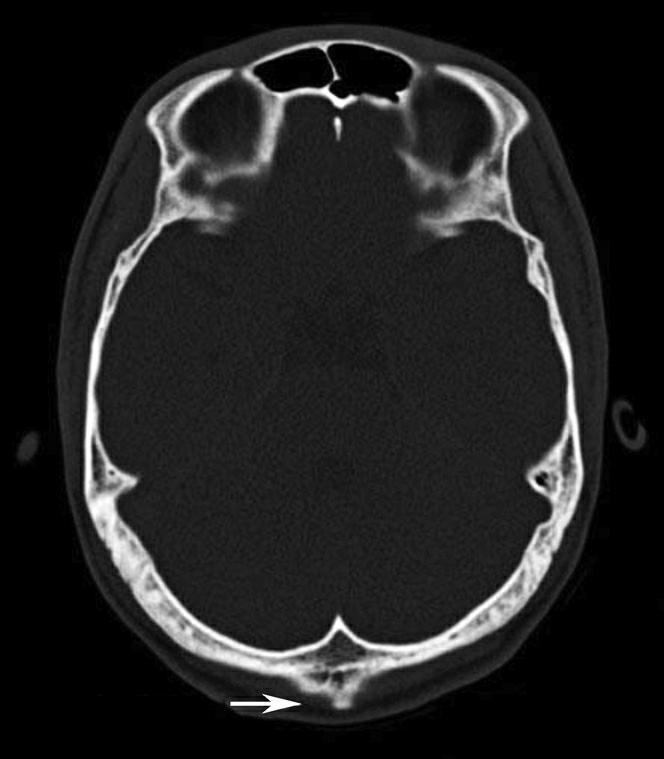

图1-2-2 颅底层面(骨窗)

A.横断面;B.横断面标注

1.鼻骨;2.筛窦纸板;3.颧骨眶突;4.翼腭窝;5.蝶骨大翼;6.卵圆孔;7.破裂孔;8.颞骨颧突;9.棘孔;10.斜坡;11.颞骨岩部;12.乳突;13.颈静脉孔;14.枕乳突缝;15.枕骨;16.枕内隆凸

层面前部呈开口向前的“V”字形,正中为鼻中隔,向两侧依次为筛窦和眼眶,眼眶内前部为眼球,后部为眶脂体。翼腭窝位于眼眶后部,窝内含有脂肪并有上颌神经通过。层面中部为蝶骨体,蝶骨体中部可见含气蝶窦,蝶窦后方为枕骨基底部,两者呈前后关系,其上面构成斜坡。蝶窦两侧为蝶骨大翼,其后外侧缘处由前向后可见卵圆孔和棘孔,分别有下颌神经和脑膜中动脉通过。斜坡外侧、岩骨尖前方为破裂孔。蝶骨大翼与眶外侧壁的颧骨借颧弓相连,颧弓和蝶骨大翼之间有咬肌及颞肌。层面中部外侧为外耳道。颞骨岩部呈“八”字形,相互之间借破裂孔软骨、蝶岩软骨结合和岩枕软骨结合连接。岩部后外侧的乳突部内可见乳突小房,乳突部与枕骨相接。岩骨后部可见颈静脉孔,内有颈内静脉、舌咽神经、迷走神经和副神经通过。层面后部为颅后窝,其内可见延髓,延髓前方为延髓前池,内有椎动脉,后外侧为小脑半球下部,后方为第四脑室、小脑扁桃体及小脑蚓部。

破裂孔、卵圆孔、棘孔及斜坡等均为重要的解剖结构,临床常见疾病如鼻咽癌常侵犯上述结构(图1-2-3)。颈静脉孔区较常见的肿瘤为颈静脉球瘤,常伴有颈静脉孔及其邻近骨质的破坏(图1-2-4)。